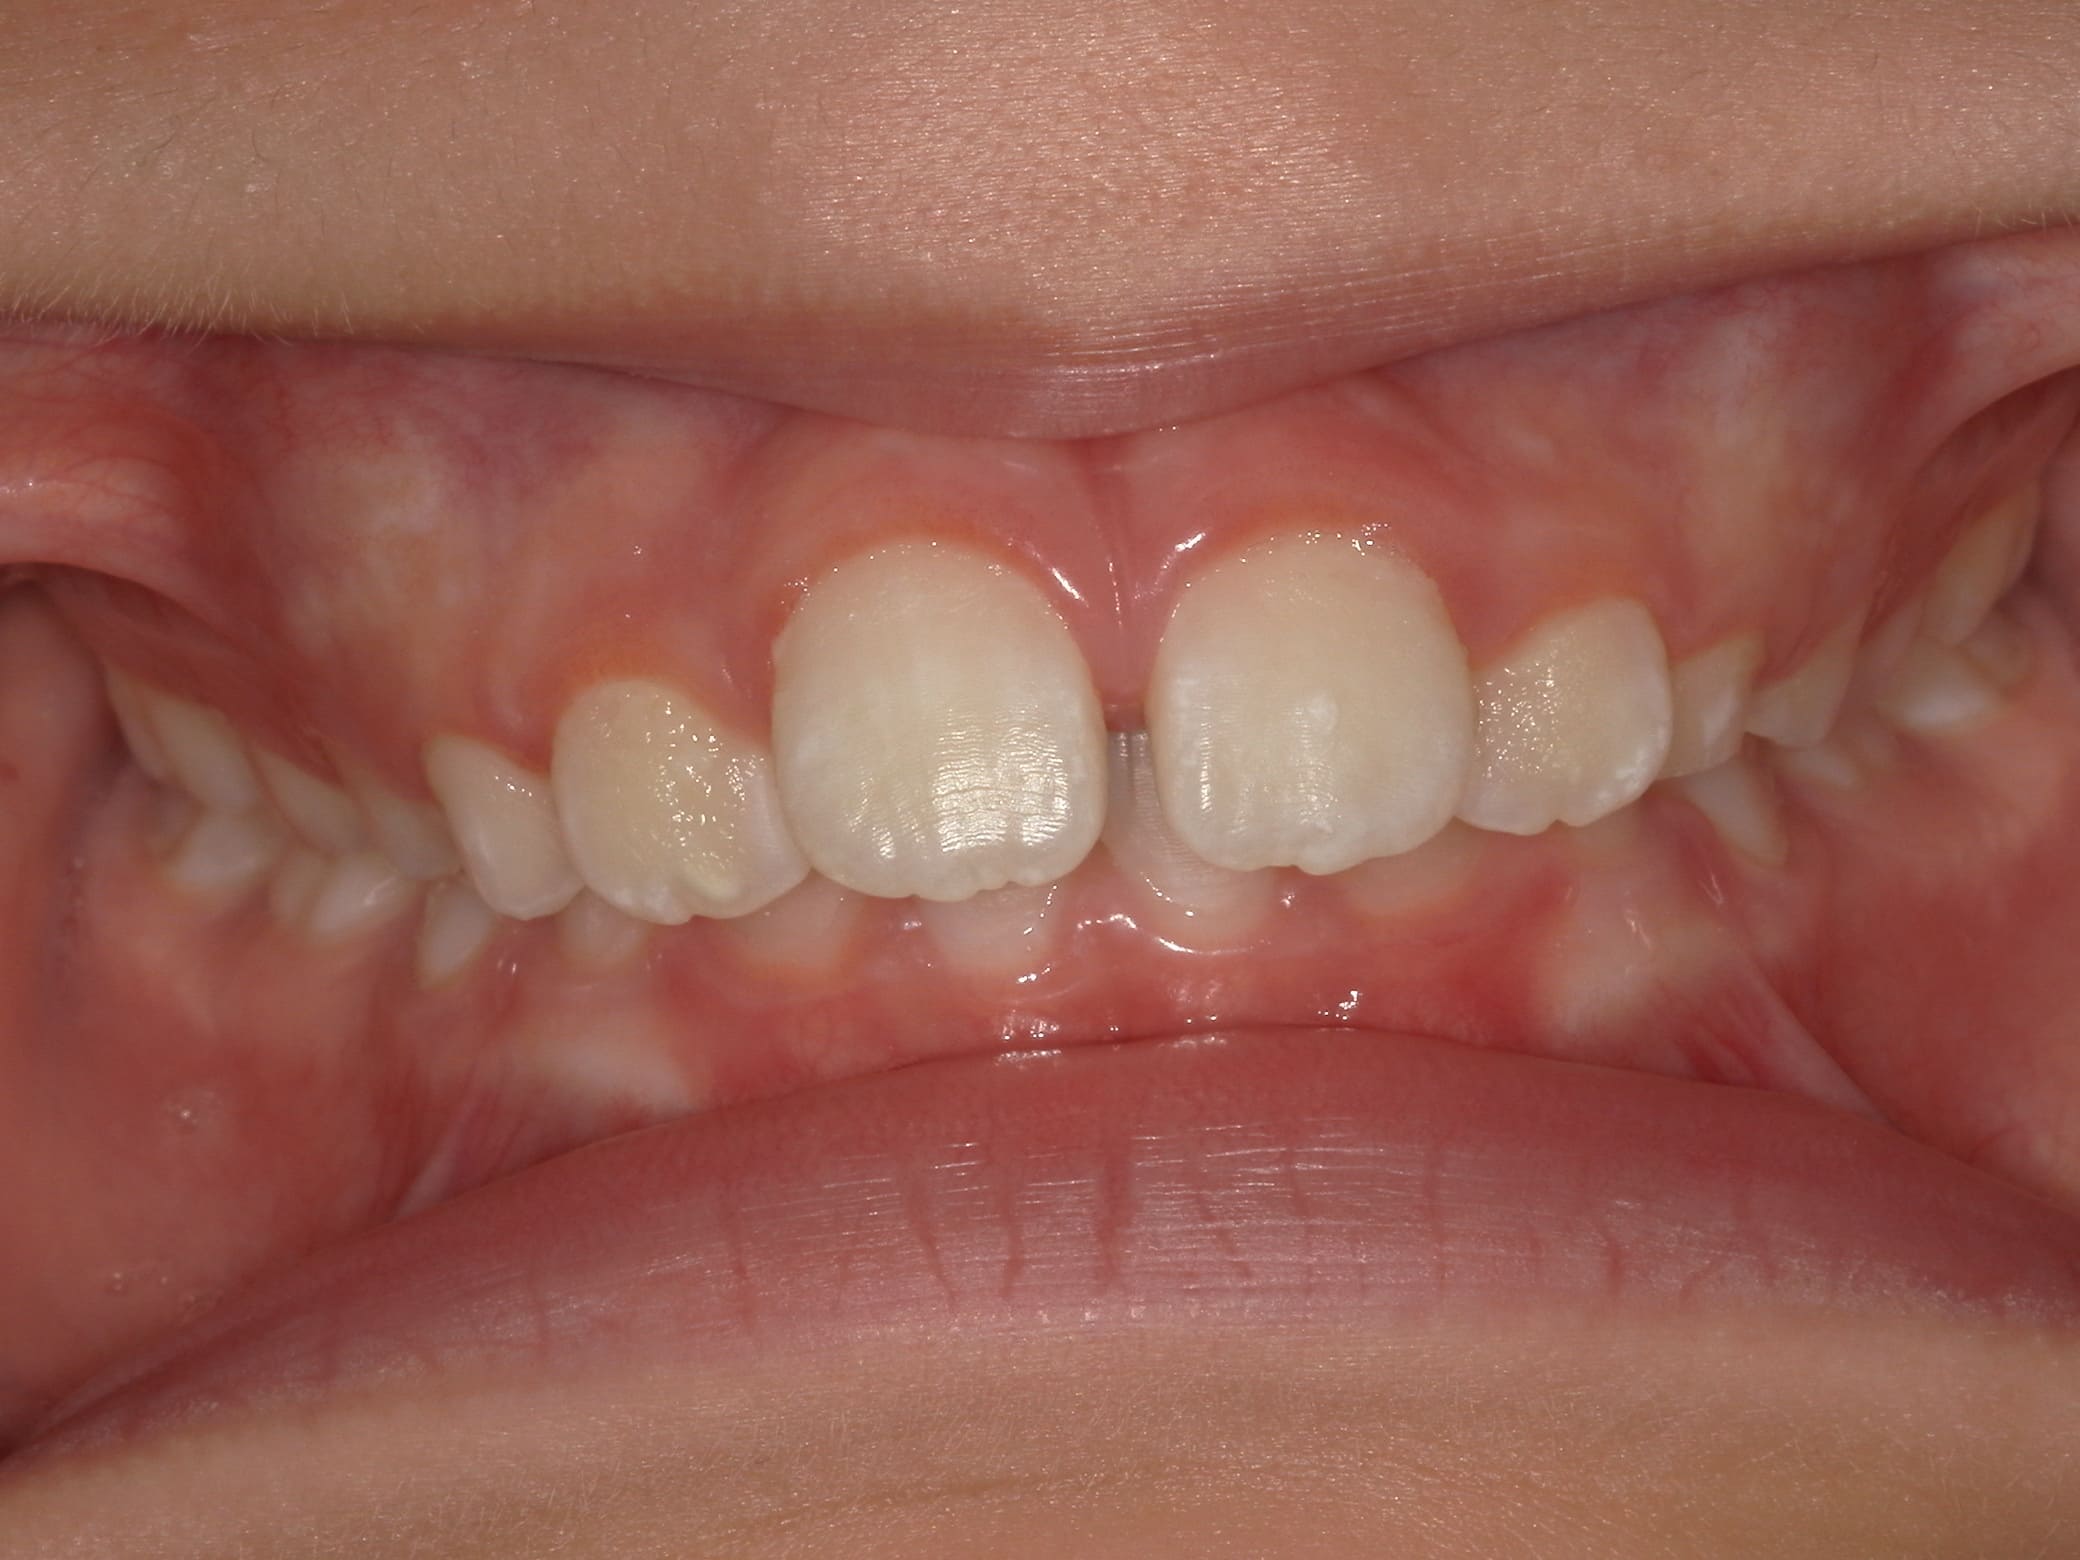

| 年齢・性別 | 8歳9ヶ月の女児 |

|---|---|

| 主訴 | 歯並びの乱れを気にされて来院された患者様です。将来的なスペース不足と歯のねじれ(翼状捻転)が懸念されました。 |

| 治療期間・回数 | 2年10ヶ月・19回 |

| 費用 | 430,000円(税別) |